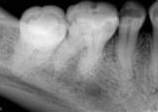

antes depois